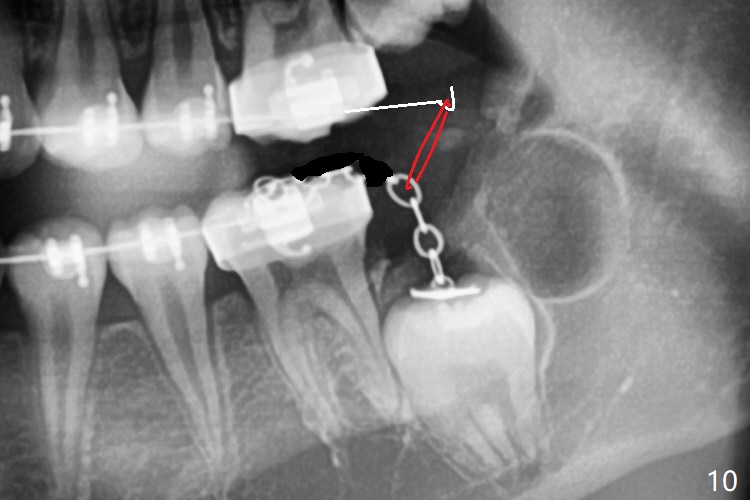

Treatment planning of surgical access to the impacted 7 (Fig.1) before CT analysis (to be canceled due to finance) include extraction of 8 (Fig.2) and removal of the bone coronal to 8 (Fig.3 red) so that there will be no bony block to 7 eruption (Fig.4). Place PRF or collagen plug in 8 socket to facilitate healing (Fig.3). Attach a retraction chain to the occlusal or buccal surface of 7 (Fig.6 pink) whenever it is convenient in term of hemorrhage and access (as mesial as possible). Remove 16 niti wires for brushing when the patient arrives. Cut 18 ss wire longer in the LL end (Fig.6 green to be bent to hook power chain (yellow)). Incision is shown as red in Fig.5. After 3 month delay, the thick buccal plate is removed from LL8 (1st) and 7 (2nd in sequence, as compared to Fig.2) to expose these unerupted teeth. In fact CT is not taken to decrease budget on the divorcing parents. A retraction chain is placed before extraction of LL8 with an intention to reduce hemorrhage (Fig.7). Although extraction requires several sectioning of the tooth, hemorrhage is mild to moderate. Instead of PRF and sticky bone (as compared to Fig.3), Osteogen plug is placed in the socket (Fig.8 OP). The bony septum between the 2 sockets is intentionally kept in place (*). 事实的确这样发生(图九:*)。埋伏牙不仅上移(^),而且远中移动(>),因为牵引方向(红虚线(橡皮筋),挂在上牙弓丝(图九:20ss:图十:18ss(之前))远端勾,积极牵引三个星期)。下次左上7放置舌侧纽扣,让病人更换橡皮筋。其实纽扣粘不住,上牙弓丝远中勾也不现实,只能使用橡皮筋挂在左上6,经常断。术后6个月,左下7继续上移(图十一)。这种低效率牵引仍然有效,牙齿继续上移,牙根长长(图十二:空箭头),但是受到左下6远中阻挡(*),所以下次在左上7咬合面装置舌侧纽扣和closed spring,改善牵拉方向(红箭头)。